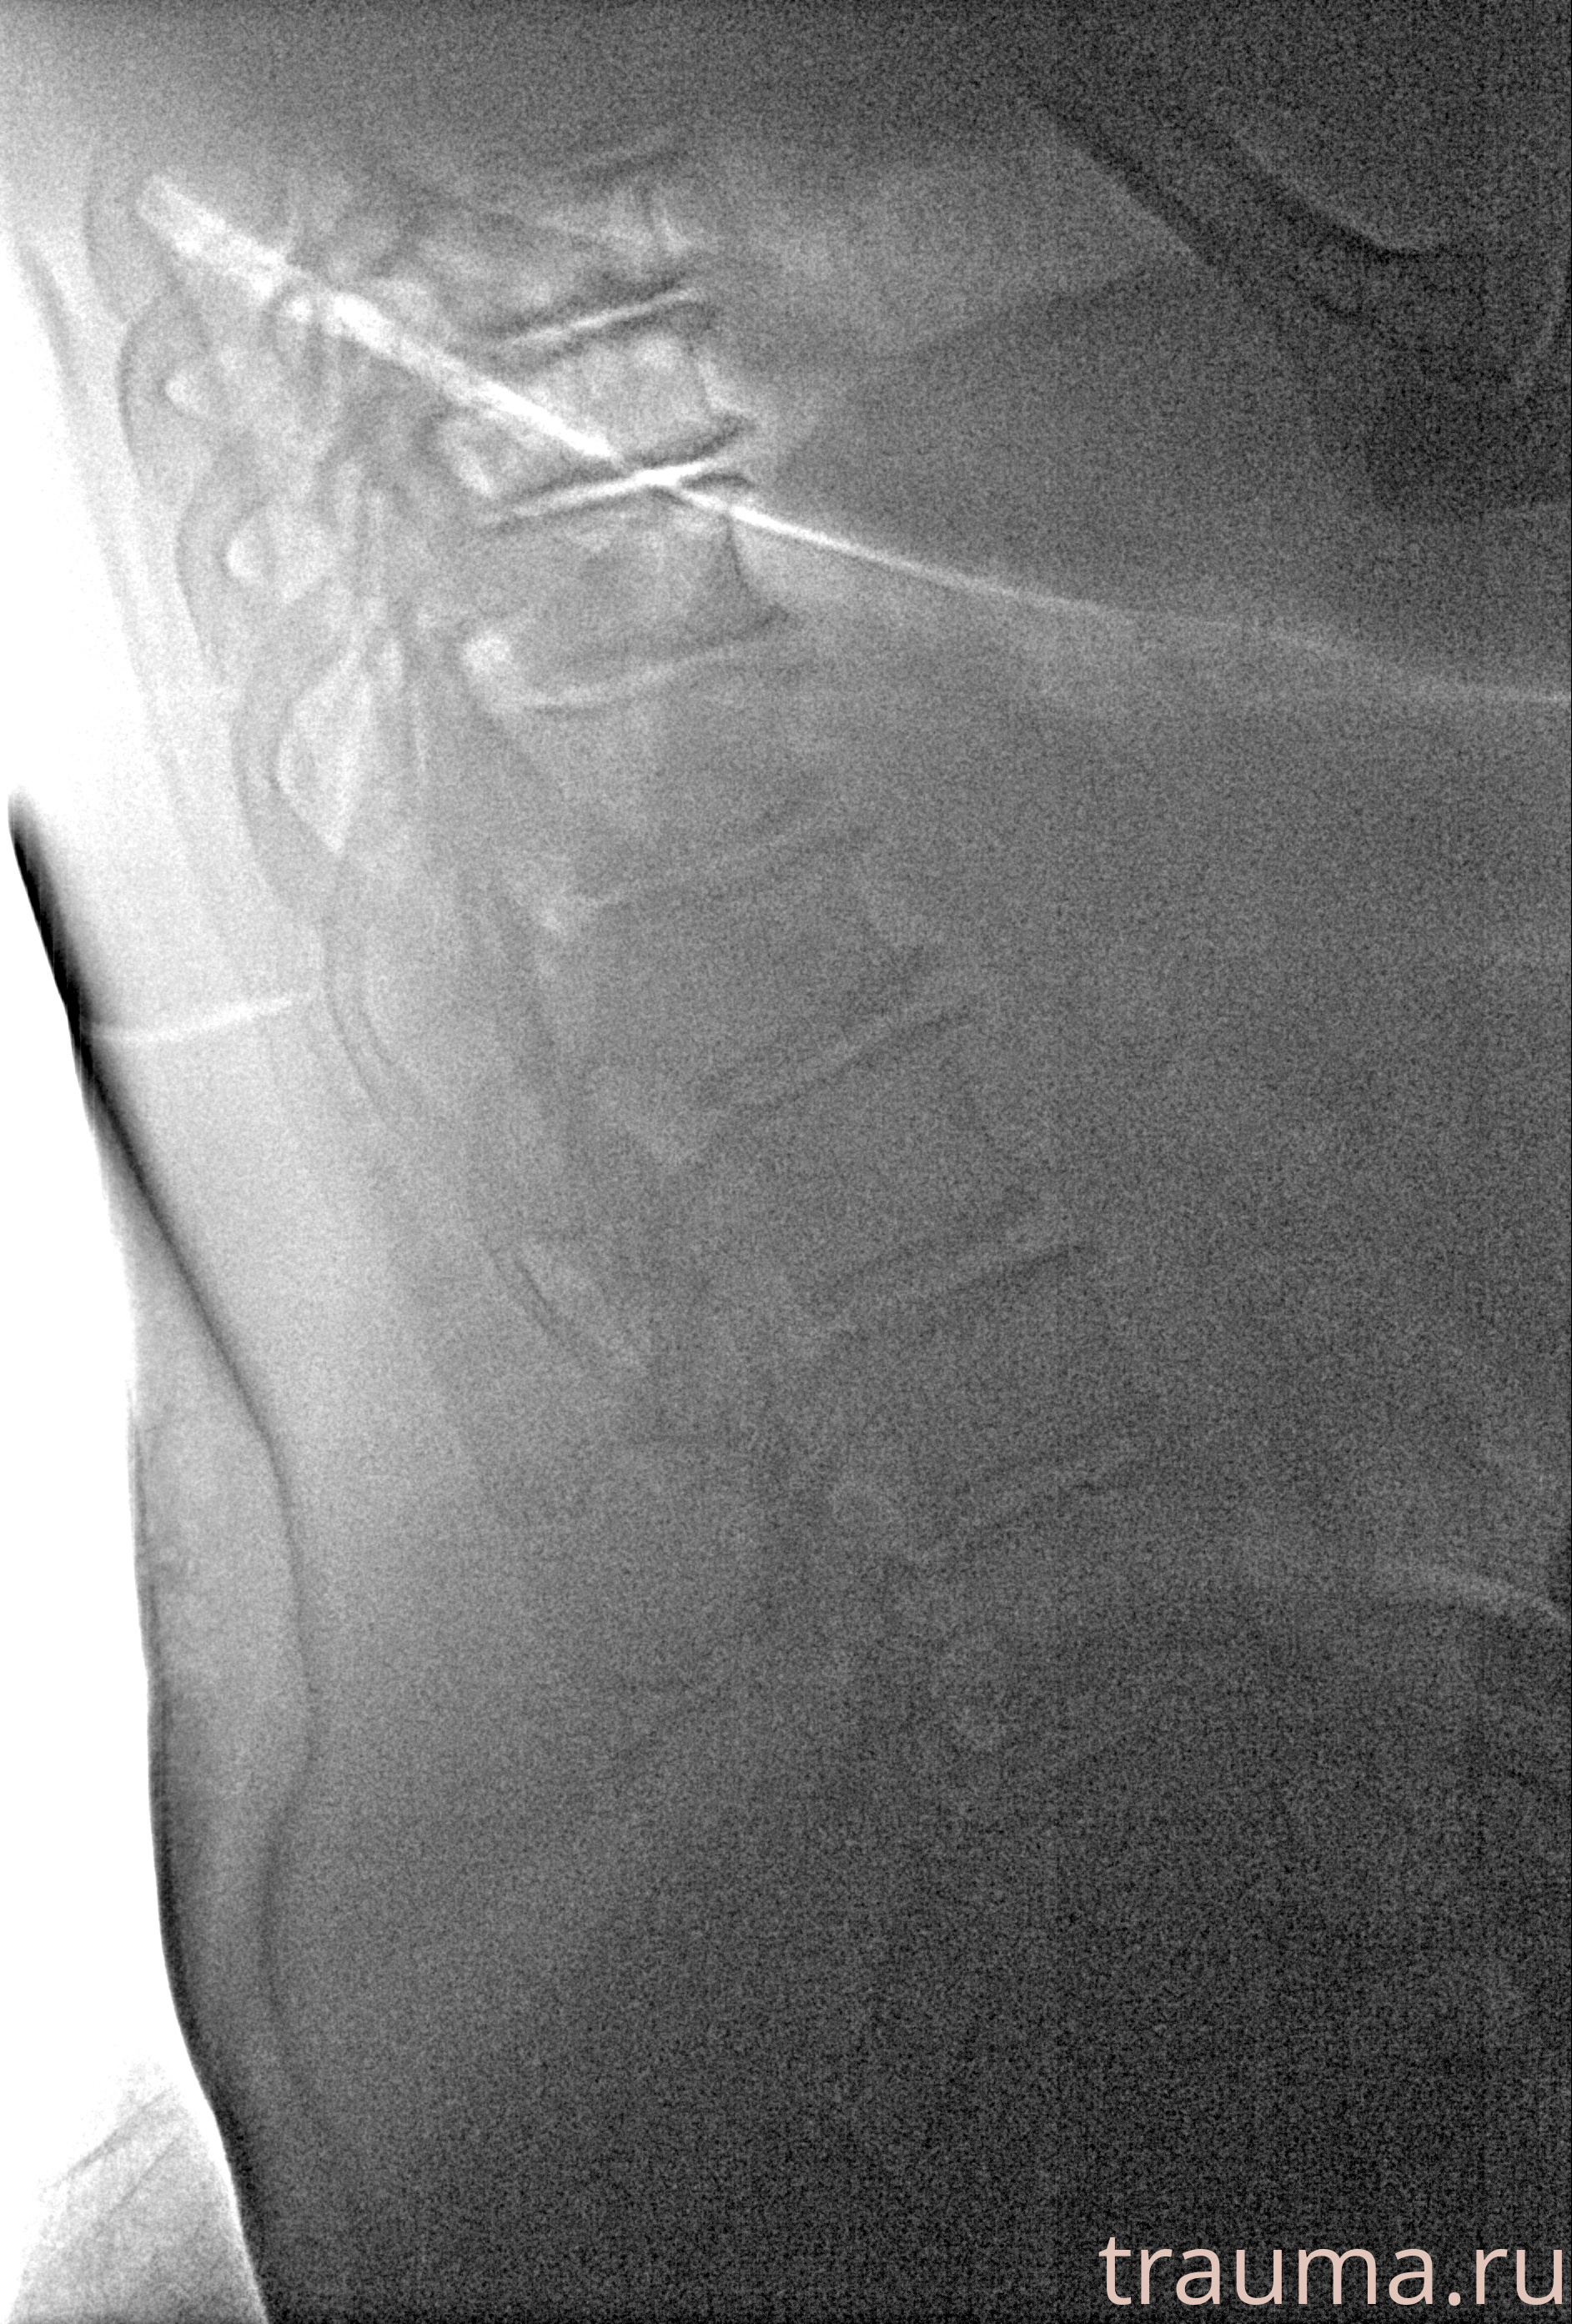

Рентгенограммы

Рентген на дому: по вашему адресу приезжает врач-рентгенолог, травматолог-ортопед с мобильным рентгеновским аппаратом, проводит диагностику травмы или заболевания, делает необходимые рентгенограммы, дает рекомендации по дальнейшему лечению. Получить качественные снимки в домашних условиях возможно благодаря уникальной методике, разработанной МосРентген Центром для института  Склифосовского